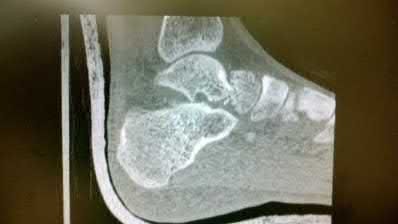

A 70-year-old female with a history of poorly controlled diabetes mellitus presents with purulent ulcers along the plantar aspect of her right forefoot and exposed metatarsal bone. She elects to undergo an amputation. She is insensate to the midfoot bilaterally. Her ankle-brachial index (ABI) for her right posterior tibial artery is 0.4. Further preoperative evaluation demonstrates a transcutaneous oxygen pressure of 45 and an albumin of 3.4. Which of the following would be a contraindication to performing a Syme amputation (ankle disarticulation) in this patient?

A Syme amputation (ankle disarticulation) is a function-preserving amputation option that allows for terminal weight bearing, however strict criteria must be met for a patient to undergo successful Syme amputation. An ankle-brachial index (ABI) less than 0.5 for the posterior tibial artery in a patient with diabetes would be a contraindication for this procedure as success is dependent on the vascular supply of posterior tibial artery to the plantar flap and heel pad.

Pinzur et al retrospectively reviewed their results when performing a single-stage Syme ankle disarticulation in patients with diabetes either for peripheral neuropathy or infection. Patients with ABIs less than 0.5 for the posterior tibial artery had significantly decreased healing rates and smokers had a three-fold increased risk of postoperative infection.